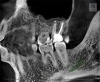

70 мкм в Эндодонтическом режиме 3,5×4 см

Высокотехнологичный детектор с самым высоким разрешением в классе – 70 мкм. Позволяет различить даже самые мелкие анатомические образования и облегчит постановку диагноза в сложных случаях. А вместе с применением алгоритма SMARF инородные тела из металла не испортят качество снимков.